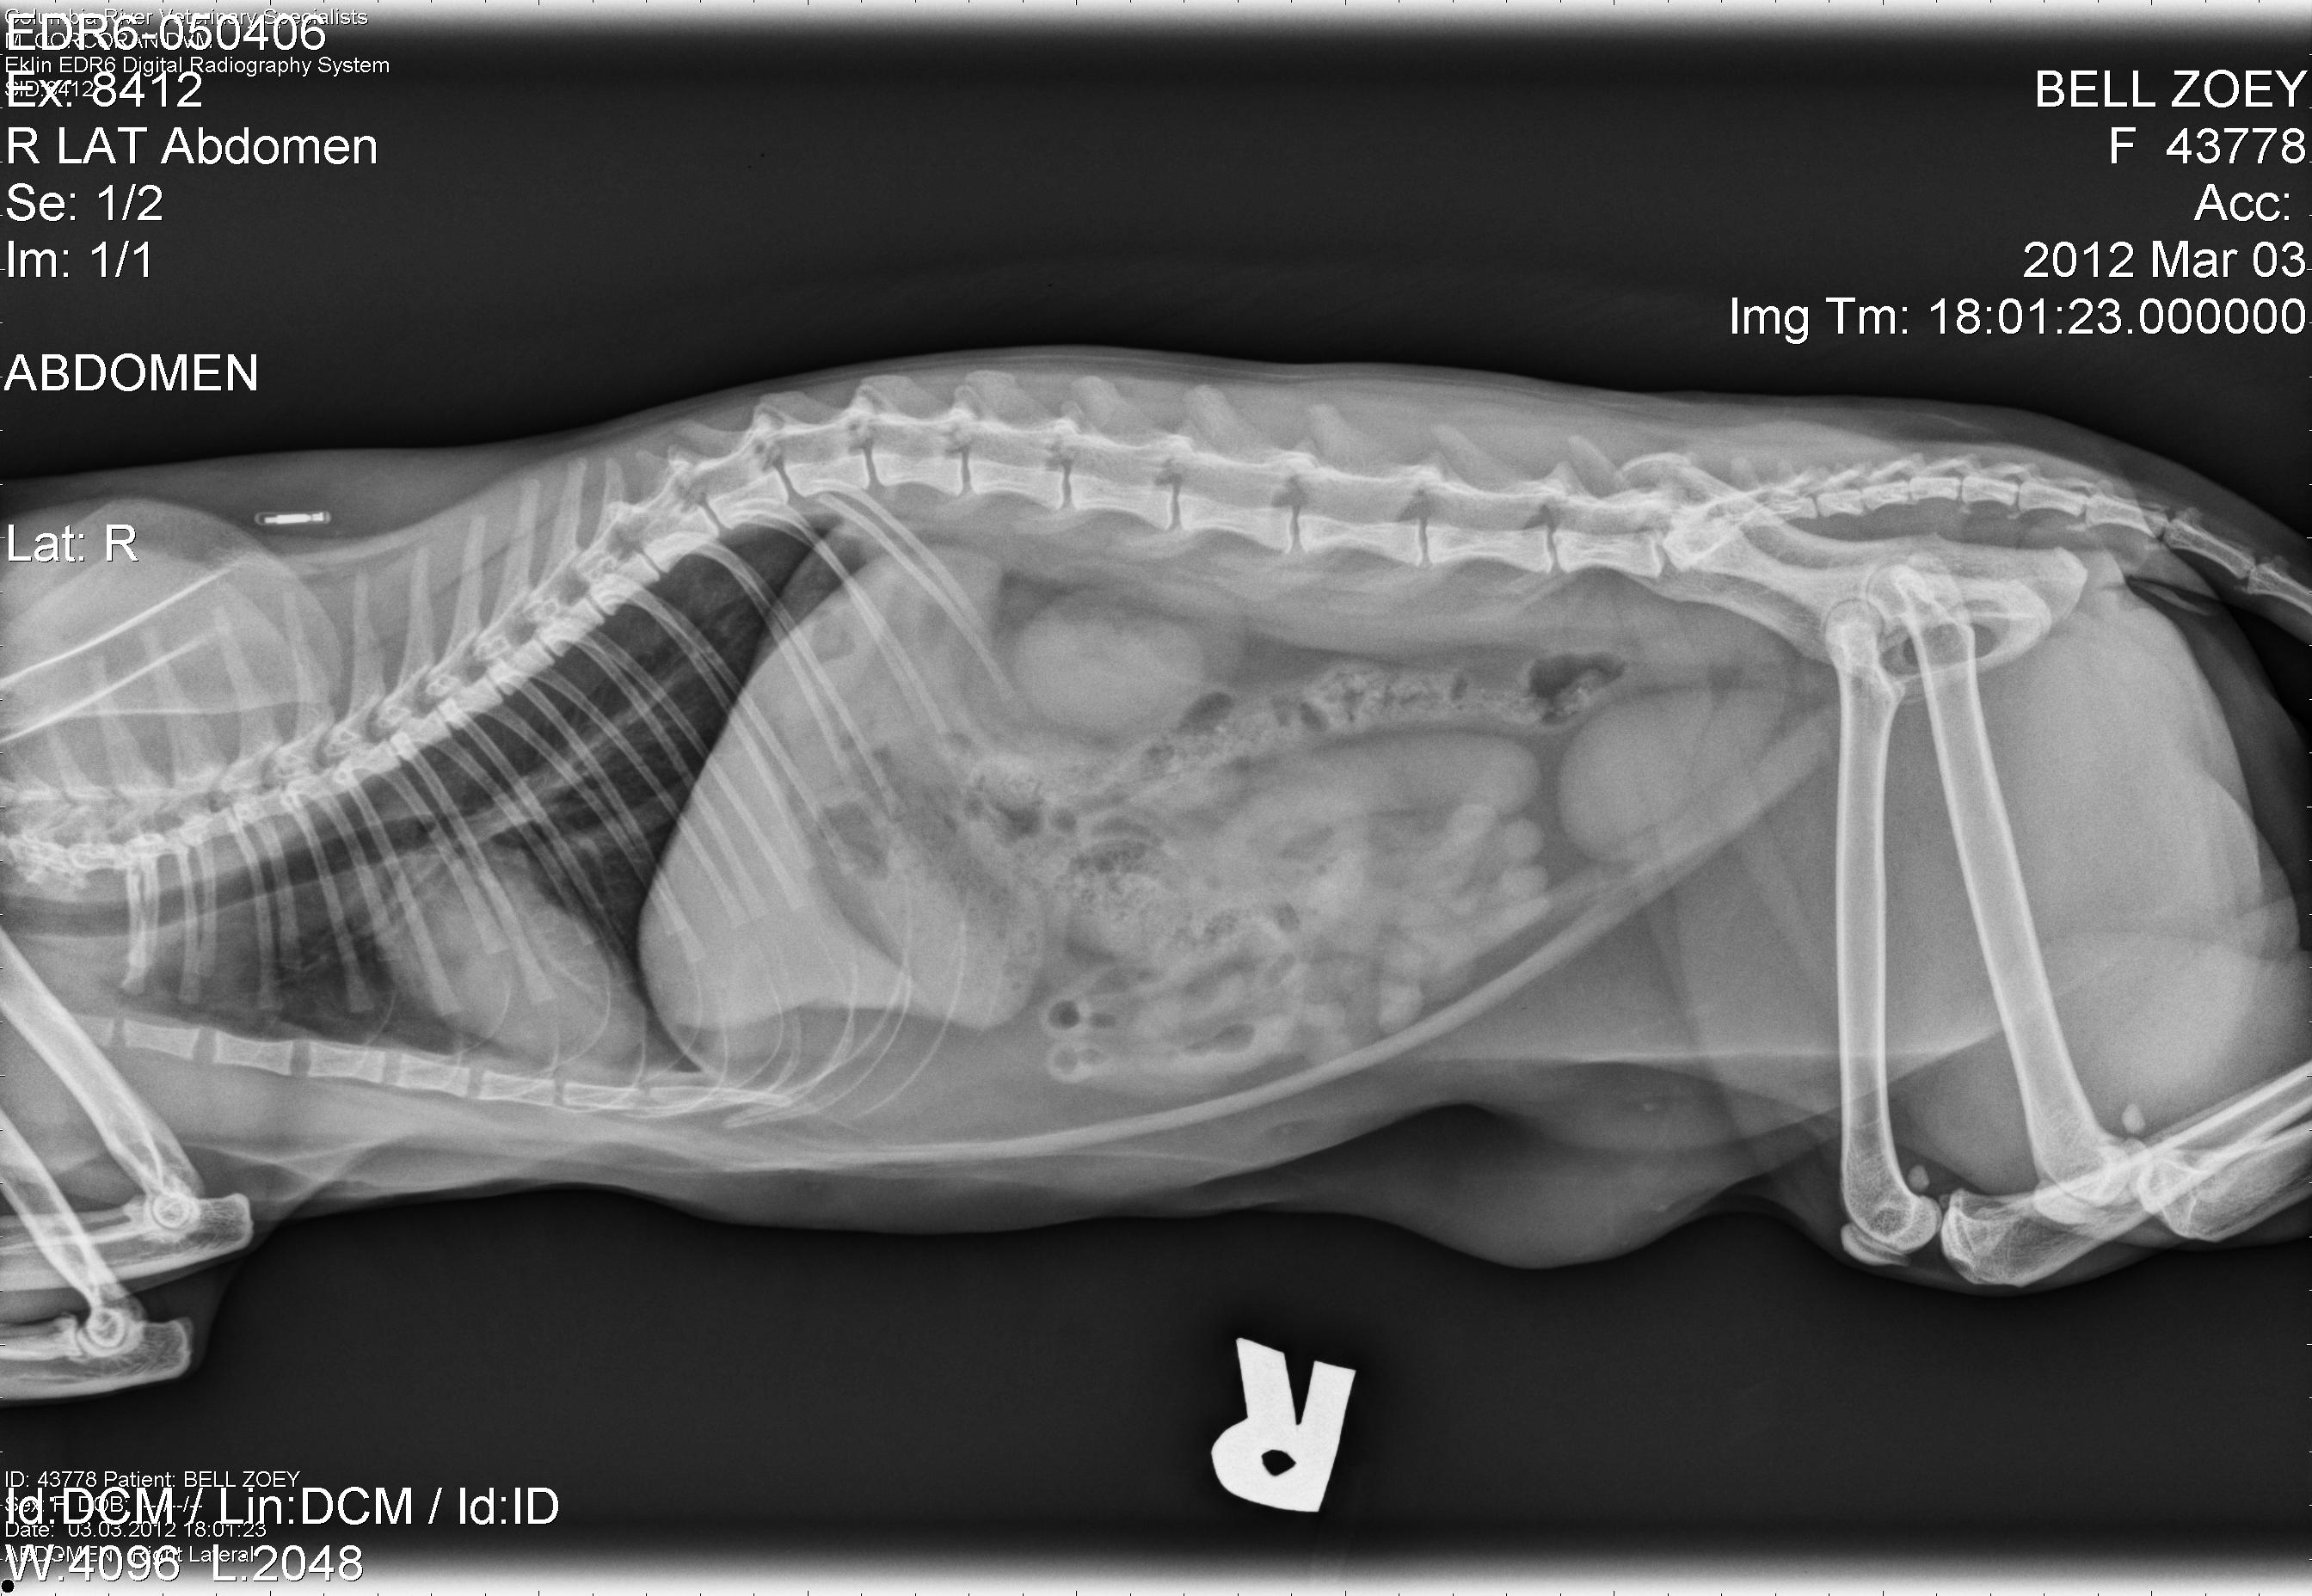

Zoey Kitty’s X-Rays!

2012, abdomen, Cat Break, Cat Stories, cat x-ray, Cats, feline, Kitties, Kitty, Kristin Bell, lateral, vet, vetrinarian, x-ray, x-raysA few weeks ago, my baby Zoey kitten had to go to the vet, because she was really sick. It turned out to be something like the flu. She had to get subcutaneous water packs and stuff, and they had to do x-rays to rule stuff out. Well, they gave me the disc with her x-rays on it, so I have her x-ray pictures to post! Pretty interesting to see! She’s doing fine now and you can see her in the last pic helping me read my book! :) Click the images for a larger viewing! :) Oh! I just noticed! In the upper left of the second image you can see her microchip!!! lol Cool!